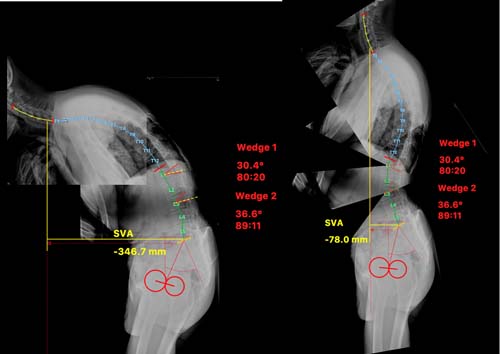

术前手术设计